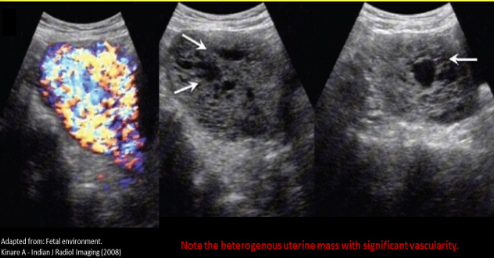

Heterogeneous with vascularity

Chorioadenoma destruens

Highly vascular complex mass